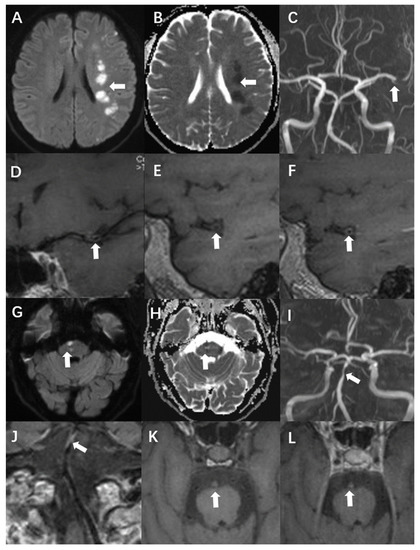

The remodelling index was calculated as the ratio of the area of the vessel zone at the culprit plaque to the vessel range at the reference site. A remodelling index higher than 1.05 was considered positive, whereas an index within 0.95–1.05 was designated as no remodelling. Finally, values smaller than 0.95 were defined as negative remodelling [16]. Another classification in this report concerned wall thickening. Centripetal thickening was defined as involvement of more than half of the arterial wall circumference. Less than 50% centripetal thickening was defined as eccentric. When the T1WI signal intensity of the culprit plaque was 150% higher than that of the ipsilateral masseter, it was defined as hyperintensity on T1WI. Significant enhancement was defined as a signal intensity close to or higher than that of the pituitary stalk [12]. Case presentations are shown in Figure 2.

Figure 2.

A 54-year-old man presented with acute infarction in the left cerebral hemisphere (A–F). No recurrence was observed during follow-up, and the sLOX-1 level was 214.46 pg/mL. (A,B): High DWI signal (white arrow) and low apparent diffusion coefficient (ADC) value (white arrow) in the left cerebral hemisphere. (C): Localised stenosis of the distal segment of the left middle cerebral artery (white arrow). (D): Localised thickening and enhancement of the distal wall of the left middle cerebral artery (white arrow). (E): Culprit plaque 3D-T1-space plain scan showed isosignal (white arrow). (F): There was no significant enhancement after the enhancement of culprit plaque (white arrow). A 69-year-old man with acute pontine infarction was diagnosed with recurrent stroke 6 months after discharge, with an sLOX-1 level of 1429.44 pg/mL (G–L). (G,H): DWI in the right pons is high (white arrow), and the ADC value is decreased (white arrow). (I): Basilar artery localised stenosis (white arrow). (J): Basilar artery wall localised thickening with enhancement (white arrow). (K): Hyperintensity was observed on the 3D-T1-space plain scan of the culprit plaque (white arrow). (L): There was no significant enhancement after enhancement of the culprit plaque (white arrow).